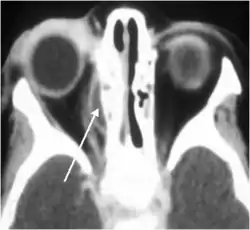

Воспаление околоносовых пазух, прежде всего клеток решётчатого лабиринта (этмоидит), в ряде случаев вовлекает в воспалительный процесс периорбиту (периостит). В некоторых случаях гнойный экссудат отслаивает периорбиту от медиальной стенки глаза с формированием субпериостального абсцесса.

![]() Этмоидит осложнился субпериостальным абсцессом медиальной стенки глазницы. Смещена медиальная прямая мышца глаза[2] |